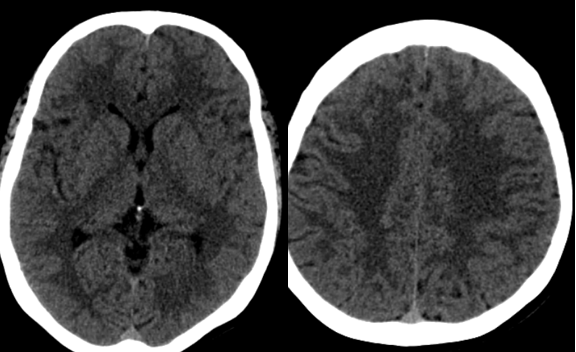

Bệnh nhân được chụp CLVT sọ não không tiêm thuốc: chưa phát hiện bất thường

Bệnh nhân tiếp tục được được chụp CLVT mạch máu não: Phát hiện hẹp khít động mạch cảnh trong trái đoạn mấu giường và động mạch não giữa đoạn M1 hai bên.